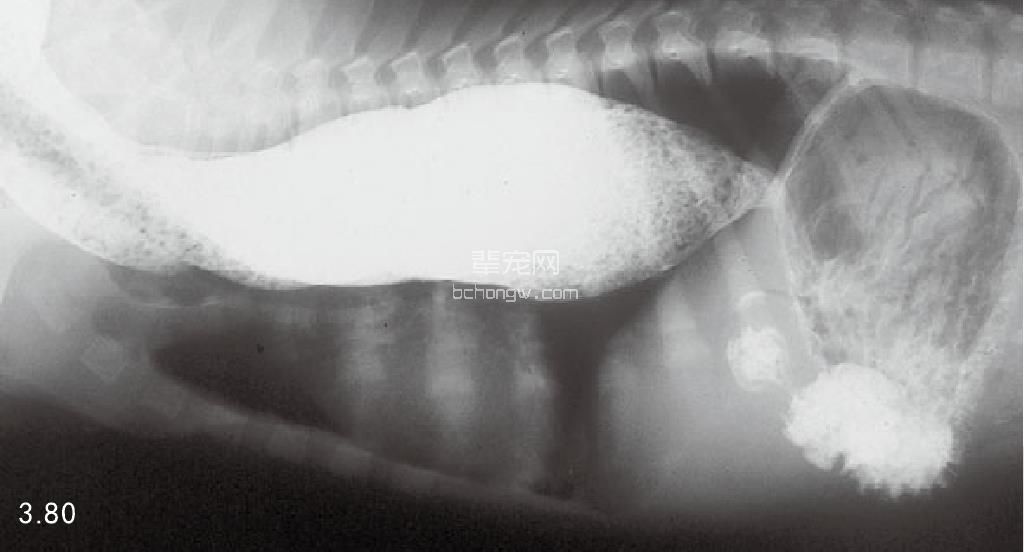

诊断 通过病史和胸腔常规X线片可以诊断 (图3.77~图3.80),但如果需要确定特殊的病 因,则需要进行额外的试验(表3.7)。如果不能 确诊可以做食管X线片和食管镜试验,但通常没有 这个必要(图3.81和图3.82)。德国牧羊犬、大丹 犬、爱尔兰赛特犬、小型雪纳瑞犬和硬毛 易患 先天性巨食管症。犬胃扩张-扭转综合征时,也 可能暂时性继发巨食管症。

图3.78和图3.79 在图3.77中所述幼犬的食道造影X线片可见食管的巨大扩张。

图3.80 11岁杂种犬特大的巨食管症与继发性肺叶尖部吸入性肺炎。没有发现神经肌肉或代谢疾病,因此将本病定为特发性巨食管症。